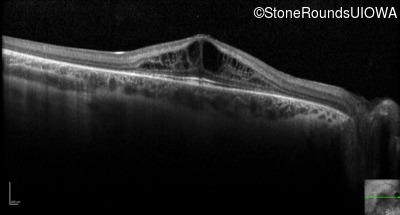

Optical Coherence Tomography - Right - 20/40 -1

Exemplar / OCT Stack

Optical Coherence Tomography - Left - 20/32 -2

Optical Coherence Tomography - Right - 20/32 -2

Optical Coherence Tomography - Left - 20/40 -1